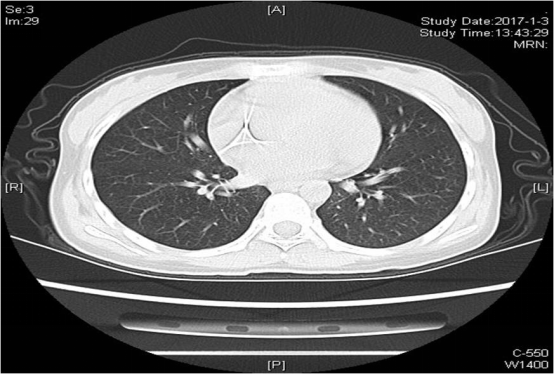

查血常规:WBC0.21×109 /L,N 6.7%,LYM 0.18×109/L,RBC 2.13×1012 /L,HBG 64.9g/L,PLT 93×109/L;PCT 0.12ng/ml;CRP 4.12mg/L;血生化:ALT 26U/L,AST 26U/L,Tbil32umol/l,TP 52g/l,GLO 14g/l,K 3.6mmol/L,Na 127mmol/L,LDH 165U/L;血氧饱和度:99%。血G试验(-);GM试验(-);血培养阴性。血浆巨细胞病毒核酸定量(CMV-DNA) 1.3×107copy/ml。胸部CT: 两肺多发腺泡结节影,边缘模糊,部分沿支气管血管束分布,并可见少许树芽征(图1)。

图 1

经过上述治疗,患者体温降至正常,咳嗽及咳痰较前好转。2017.1.3复查肺部CT(图2)较前明显好转。

图 2